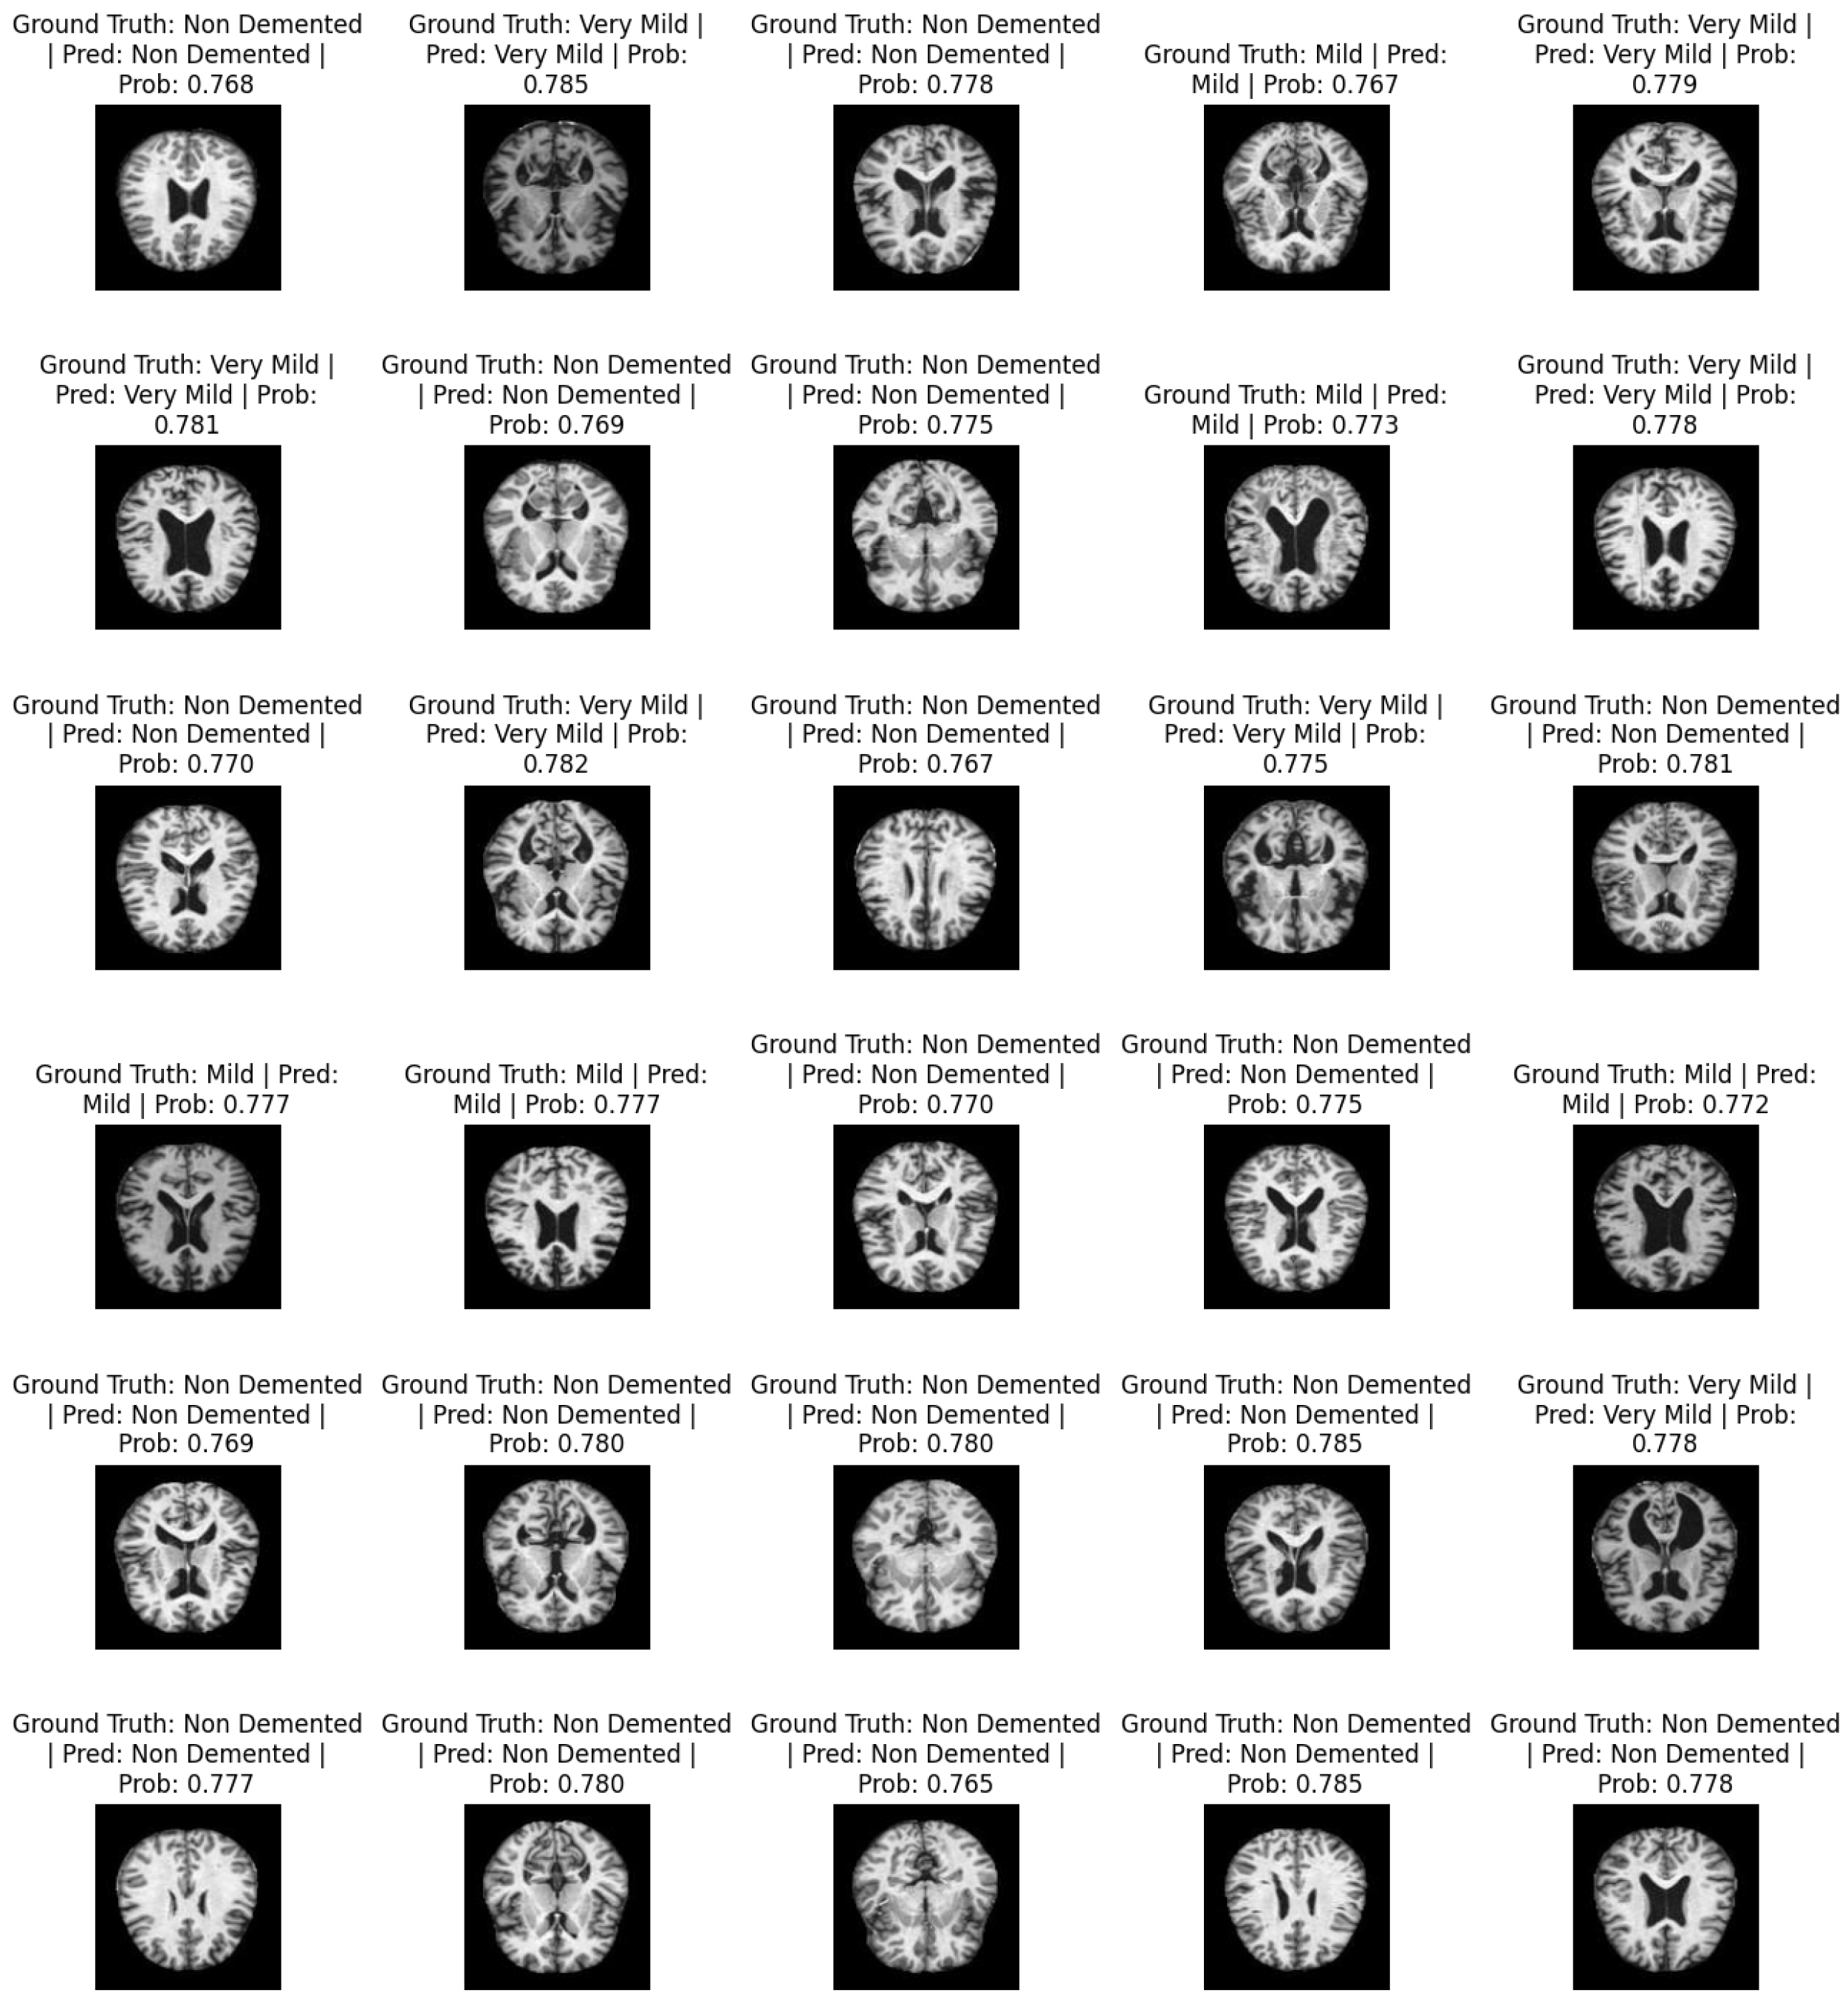

Figure 4 shows a sample of predicted images. It contains information about the actual labels and predicted labels: i.e., ground truth and prediction. For each image, the classification probabilities ranging from 0 and 1 show the probability of the image being classified as one of the respective classes. The total number of classes is non-demented, mild, moderate demented, and very mild.

Figure 4. Predicted AD classification.

Mathematics 13 01927 g004